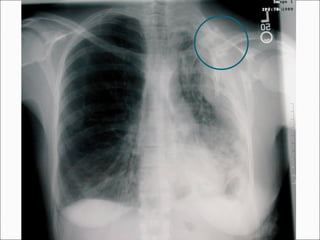

Injuries Associated with

Sternoclavicular Joint Dislocations

 Mediastinal

Compression

 Pneumothorax

 Laceration of the

superior vena cava

 Tracheal erosion

From Wirth MA and Rockwood CA, JAAOS, 4:268, 1996